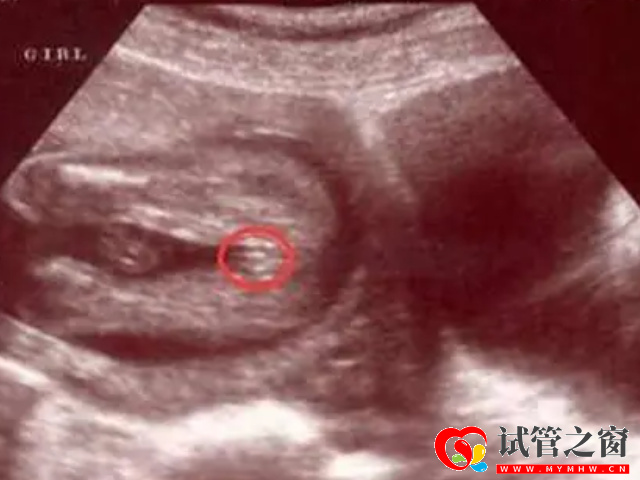

- 1. 可以看胎儿双腿之间,如果说这个部位是有三条白线,而且呈小凹槽状、圆圆的,大概率怀的是女孩,如果是凸出的东西,大概率是男孩;

- 4. 你还可以观察四维彩超单的结果,如果是双侧肾盂明显分离,表示是男孩,如果是双侧肾盂没有明显分开,就是女孩;